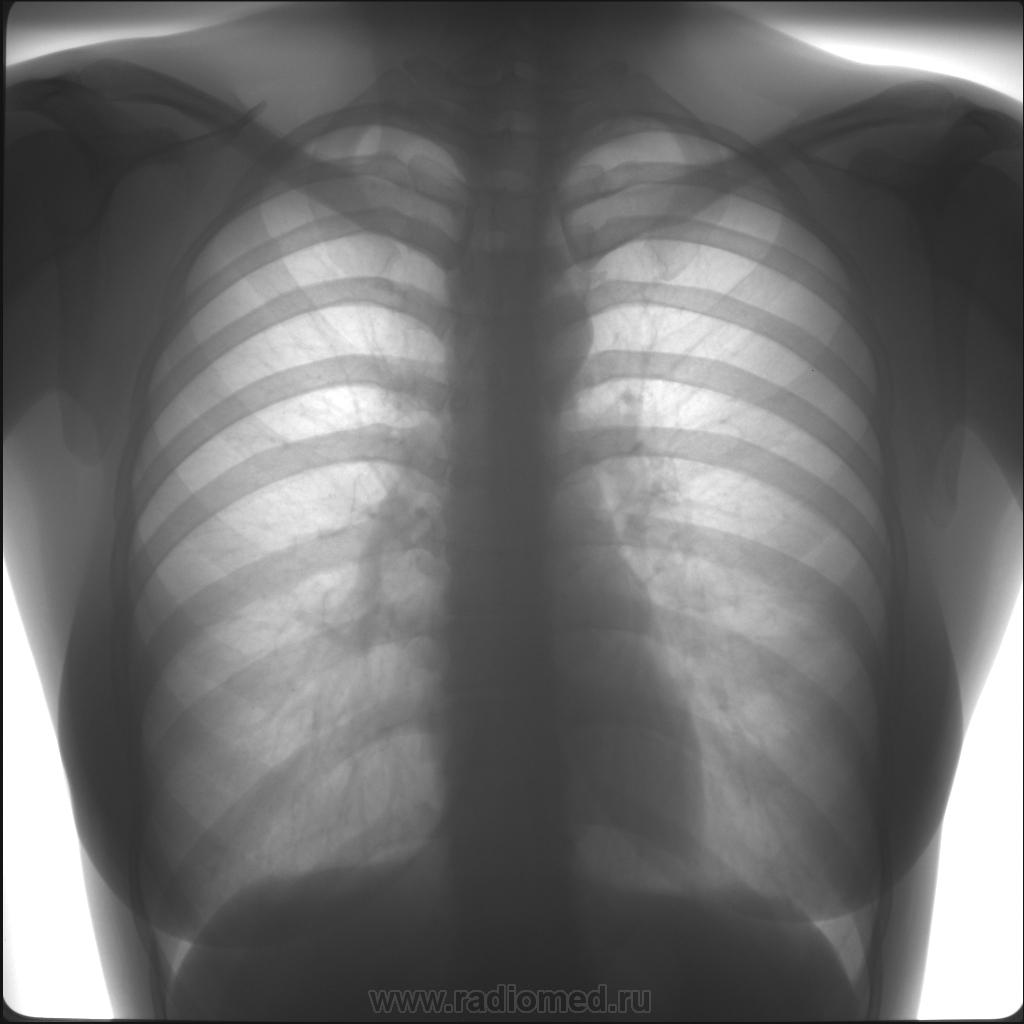

Нормальная рентгенограмма легких: что нужно знать

Раздел: Мудрость в объективе